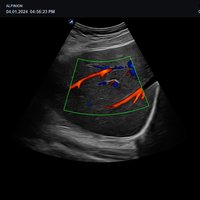

• Gefäße

• L3-15H (3-15 MHz) für Ultraschalluntersuchungen in den Bereichen Gefäße, Weichteile, Bewegungsapparat (MSK)

• L3-12H WD (3-12 MHz) für Ultraschalluntersuchungen in den Bereichen Gefäße, Weichteile, Bewegungsapparat (MSK), Pädiatrie

• L3-8H (3-8 MHz) für Ultraschalluntersuchungen in den Bereichen Gefäße, Bewegungsapparat (MSK), Pädiatrie

• P1-5CT (1-5 MHz) für Ultraschalluntersuchungen in den Bereichen Echokardiographie, Abdomen, Gefäße